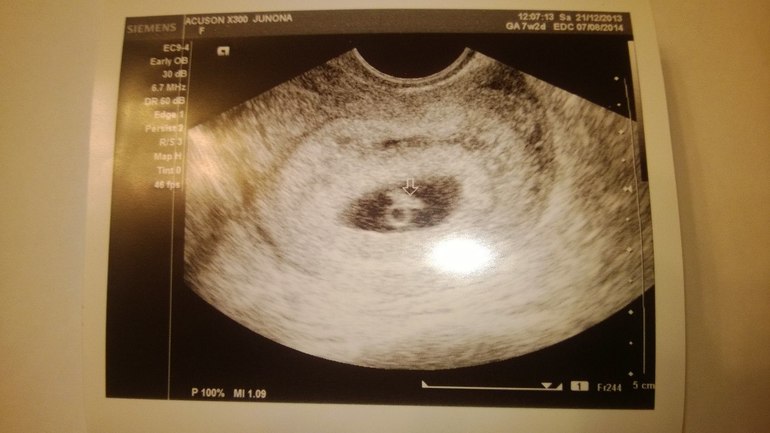

Наше первое УЗИ!))

УЗИ, КТГ, доплерВот и сходила я,для спокойствия души!))Это мы!!!

Срок получается чуток меньше,чего и следовало ожидать в связи с поздней О!

Главное сердцебиение есть,и мы в матке как надо!

КТР у нас было на тот момент на 6,4))Это по эмбриону,но акушерский.У меня просто поздняя О была...